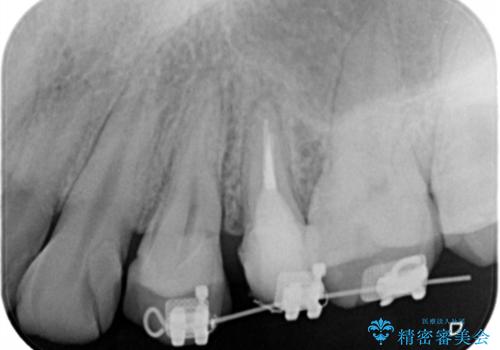

- 歯ぐきの腫れや、歯の内部が黒く見えることからの虫歯の治療を求めて来院されました。

虫歯が大きかったことから、神経の温存はできたものの歯ぐきよりも深い虫歯の問題を解決するため、部分矯正治療を併用したセラミック治療を行うこととしました。

当初、歯ぐきよりも深い虫歯の存在や、歯のポジションに問題がありましたがマルチブラケットを用いた部分矯正で行うことで歯の挺出同時に適切な位置へと歯を移動させ、歯周環境を整えたセラミック治療を行うことができました。